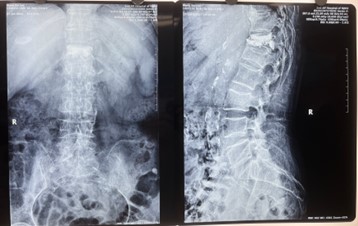

对比一些9英寸的平板C形臂,华体会体育登入首页PLX119C大平板C形臂,30CM*30CM想(30CM*30CM)的成像范围,一次性可成像5节腰椎,有效减少小视野C形臂难以一次性确定伤椎,可能需要进行多次拍摄的问题,使得手术效率更快、更准确。